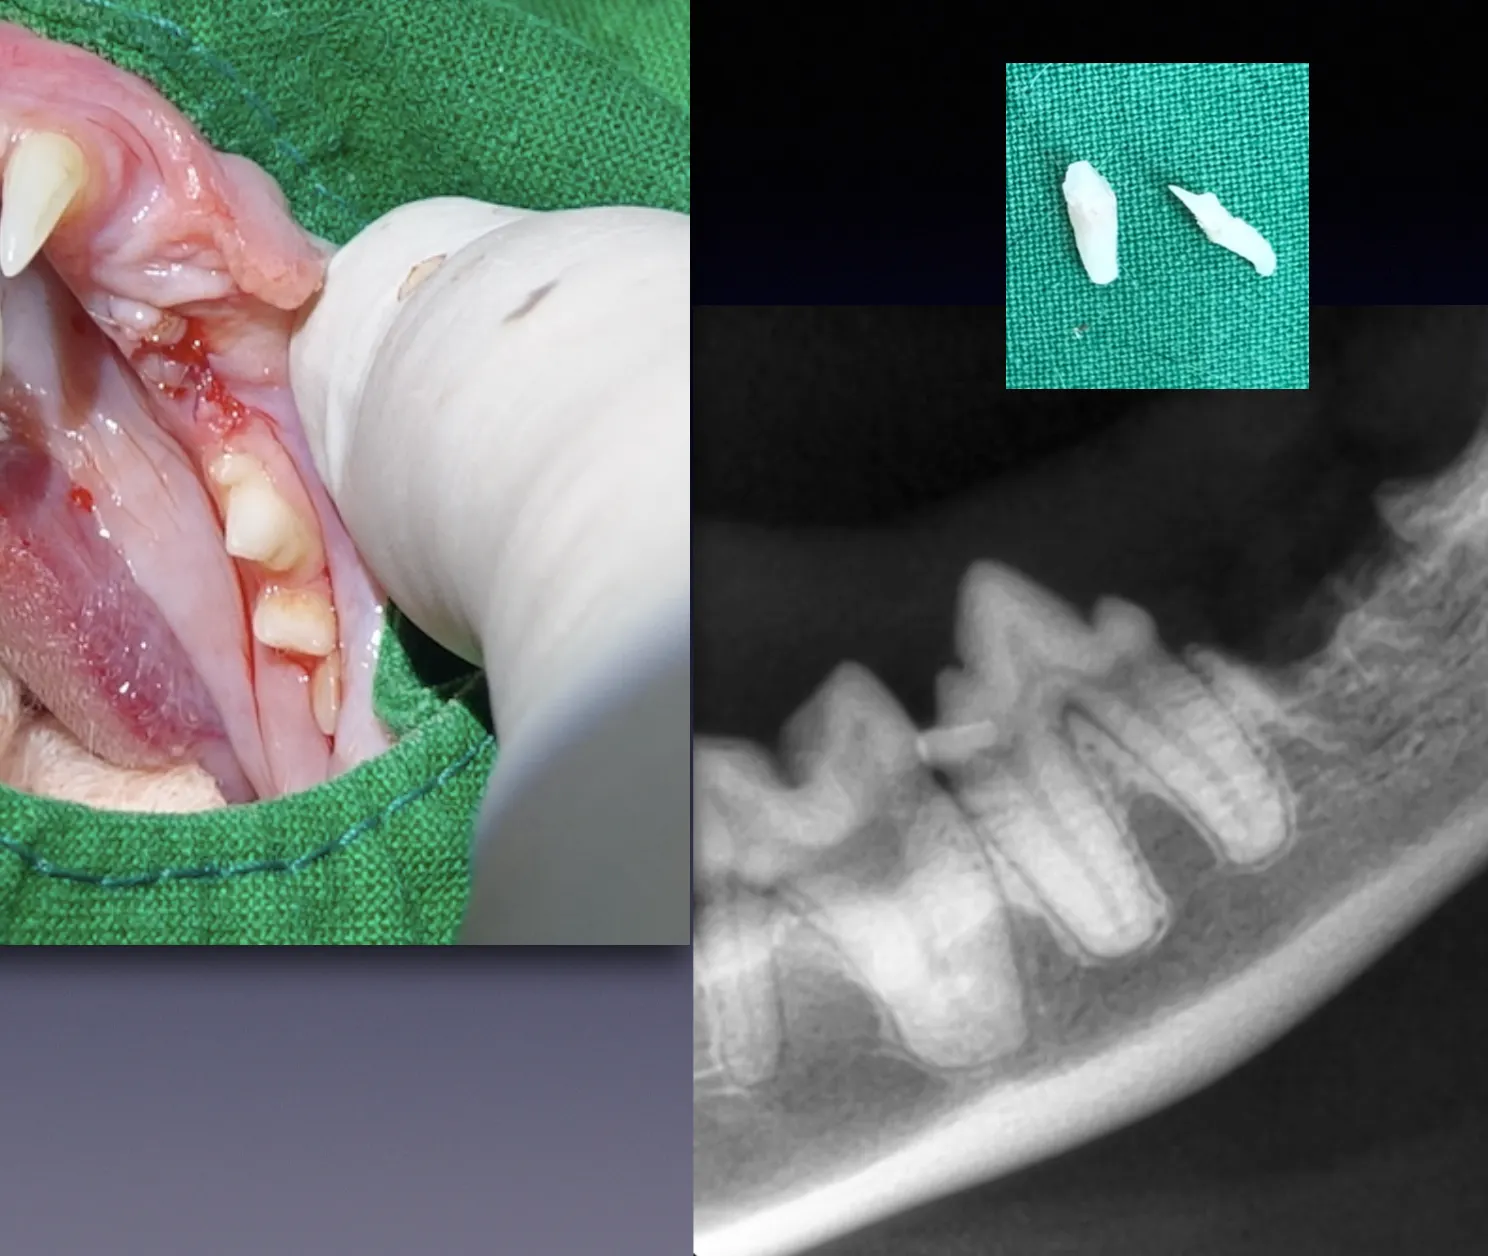

우선 전신 마취 후 치아방사선 촬영 후

치아 뿌리의 상태를 확인하고

치아흡수성 병변이 관찰되는 경우

발치를 진행합니다.

이영수 고양이 치과 클리닉 에서는

스케일링 시 치아 방사선 촬영을

항상 진행하고 있으며,

이를 통해 불필요한 마취 횟수를 줄이며

정확한 진단을 통해

발치가 필요한 경우

스케일링 후 보호자분께 설명 후

안전하게 발치를 진행하고

있습니다.